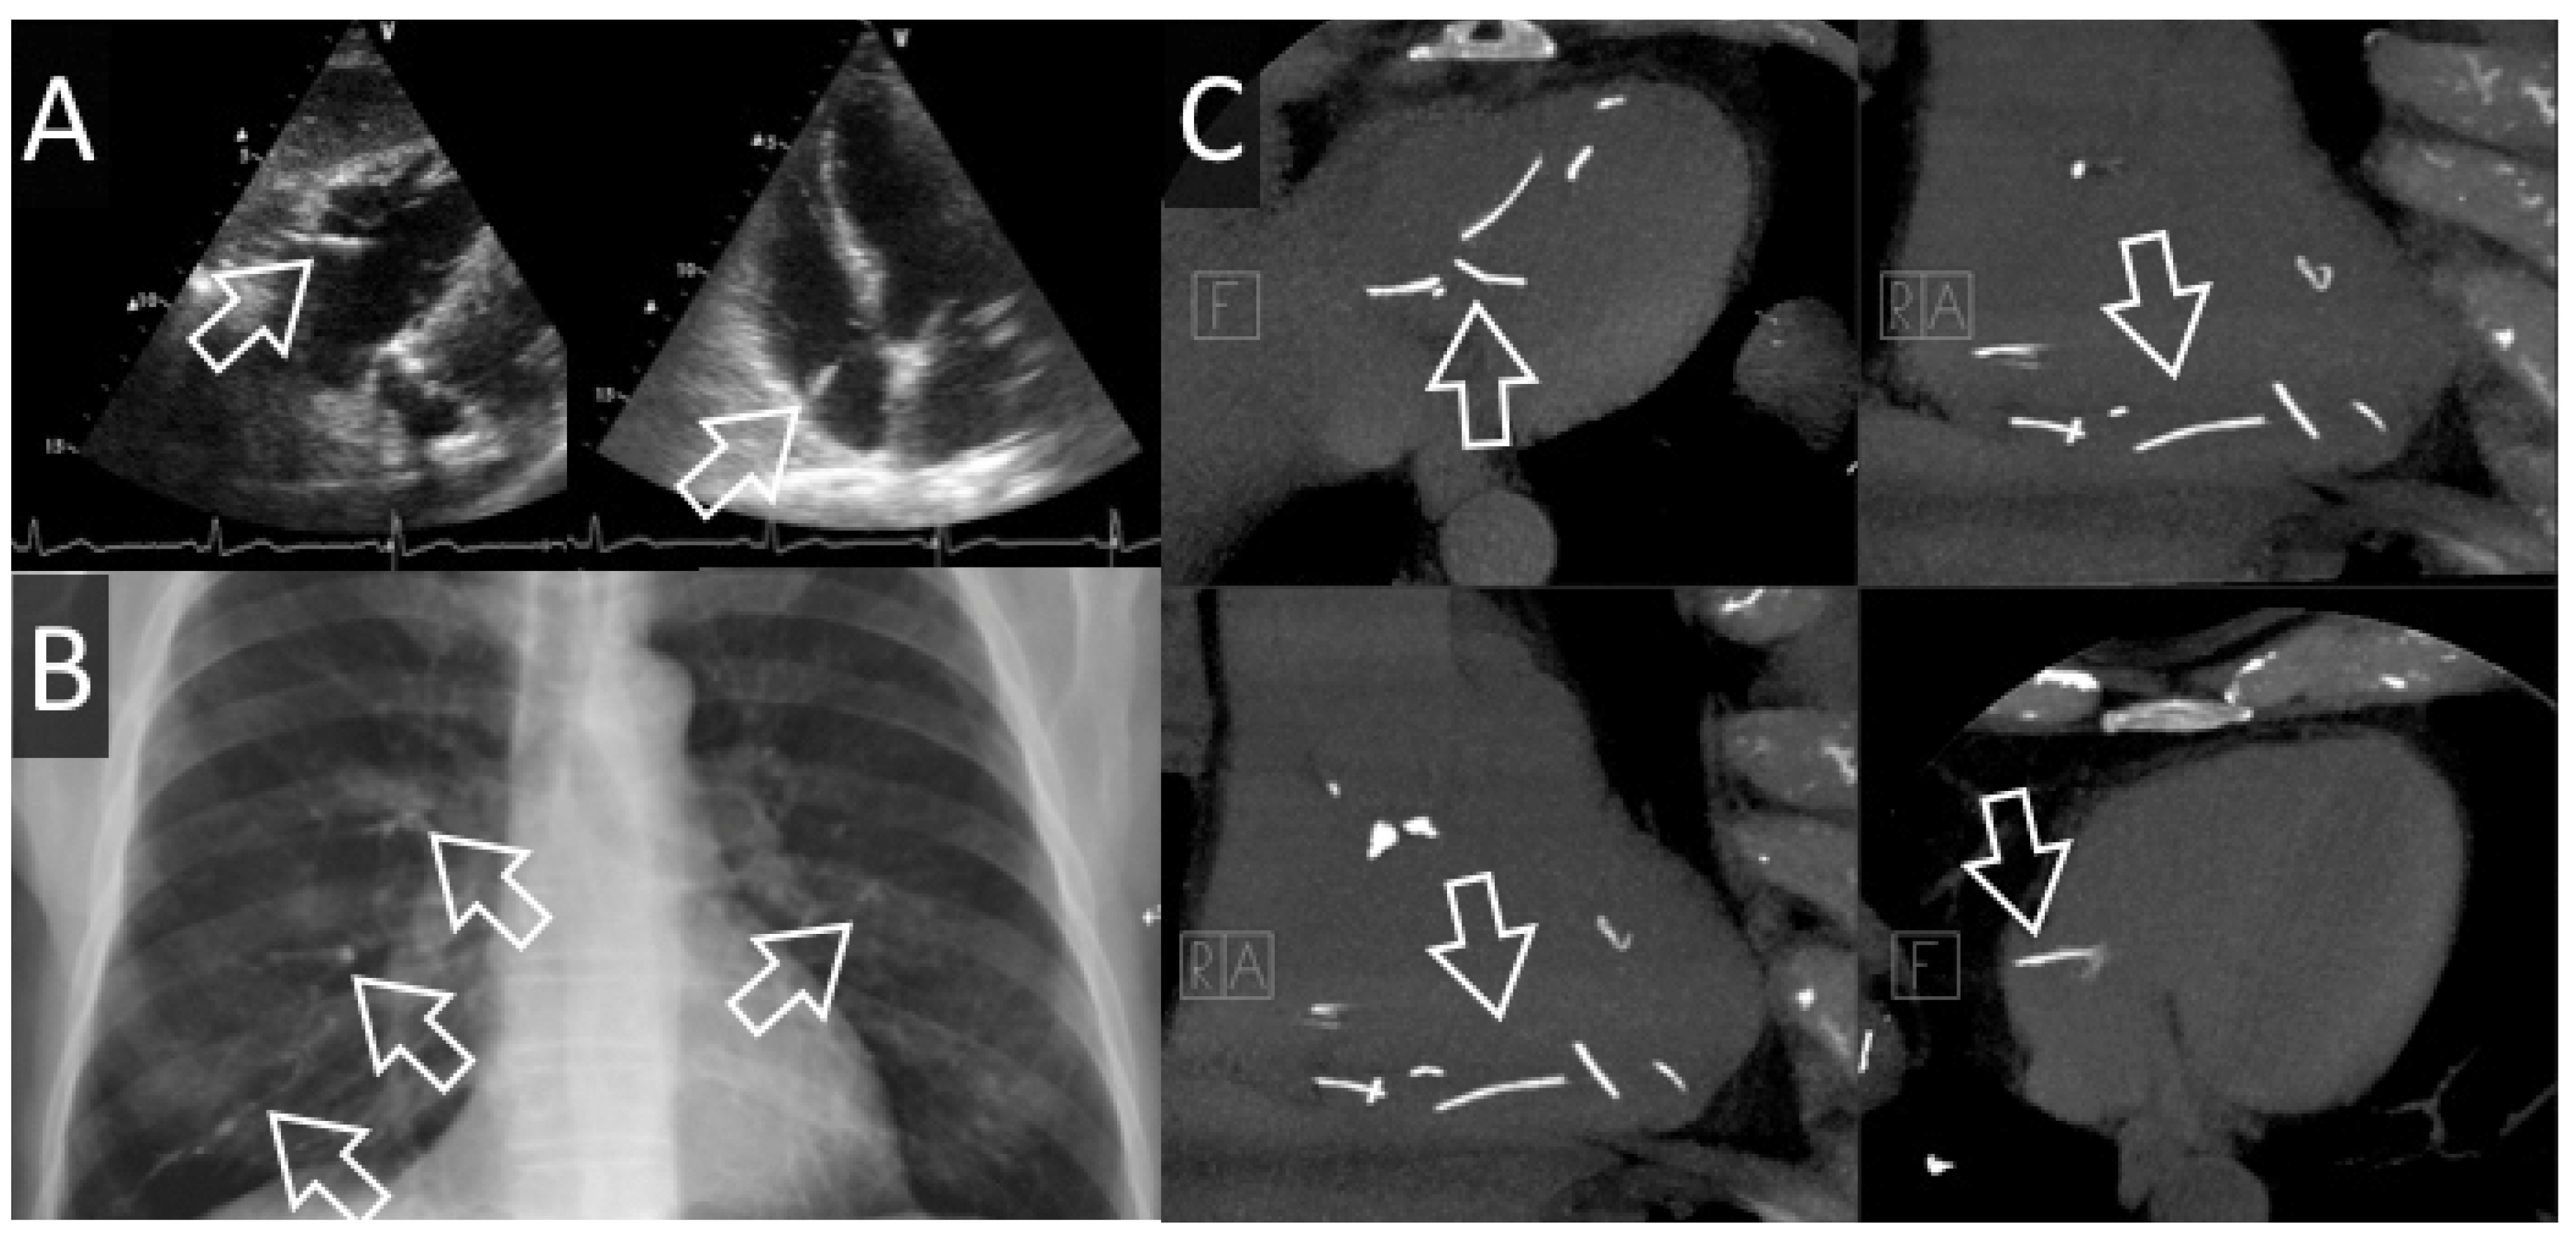

Figure 1. Cas #1. Panel A. ECG après découverte de l’embolisation pulmonaire, Panels B, C, D. Embolisation de ciment dans l’artère pulmonaire droite visible à l’artériographie pulmonaire avant (B&C) et après (D) tentative d’extraction.

Une patiente de 49 ans bénéficie d’une cyphoplastie T10 et d’une vertébroplastie L5 pour des fractures tassements symptomatiques survenues dans un contexte de lymphome T sous chimiothérapie. Durant l’intervention, une fuite de ciment est visualisée dans une veine péri-vertébrale et une embolisation pulmonaire est constatée sous scopie, sans instabilité hémodynamique. Après l’intervention orthopédique, la patiente est directement transférée en salle de cathétérisme cardiaque: l’embole est confirmé au niveau de l’artère pulmonaire inférieure droite et une extraction percutanée est tentée sans succès. Il n’y a pas d’hypertension pulmonaire secondaire à l’embolisation. La surveillance hémodynamique et échocardiographique est sans particularité. Les enzymes cardiaques (BNP/troponine hs) restent dans les limites de la norme.

La patiente est mise au bénéfice d’une anticoagulation orale empirique (Xarelto®) pour une durée de 12 mois. Les contrôles cliniques et échocardiographiques effectués à 6 et à 12 mois de l’embolisation sont dans les limites de la norme. Il n’y a pas de changement de taille de l’embole sur les 12 mois de suivi.